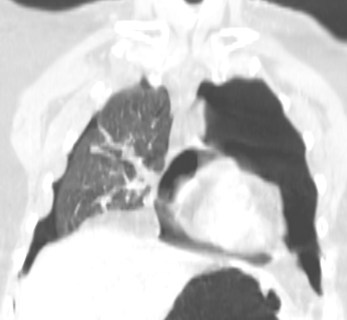

Signo del diafragma continuo en un paciente con neumopericardio. Se trataba de un accidente con traumatismo torácico. La radiografía muestra algunas fracturas costales izquierdas, un foco contusivo en campo medio izquierdo y un diafragma continuo. La reconstrucción coronal de TC demuestra que se trata de un neumopericardio. Además existe un neumotórax bilateral, más cuantioso en el hemitórax izquierdo.